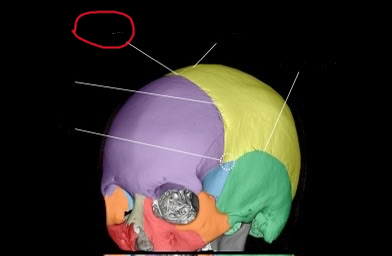

anth 1400 lab exam 1 cranial, skull shit

sphenoid bone (lateral)

also greater wing

frontal bone (lateral)

ethmoid bone (lateral)

also orbital plate

temporal bone (lateral)

occipital bone (lateral)

parietal bone (lateral)

coronal suture (lateral)

pterion

coronal suture (suture)

bregma

sagittal suture

squamosal suture

lambdoid suture